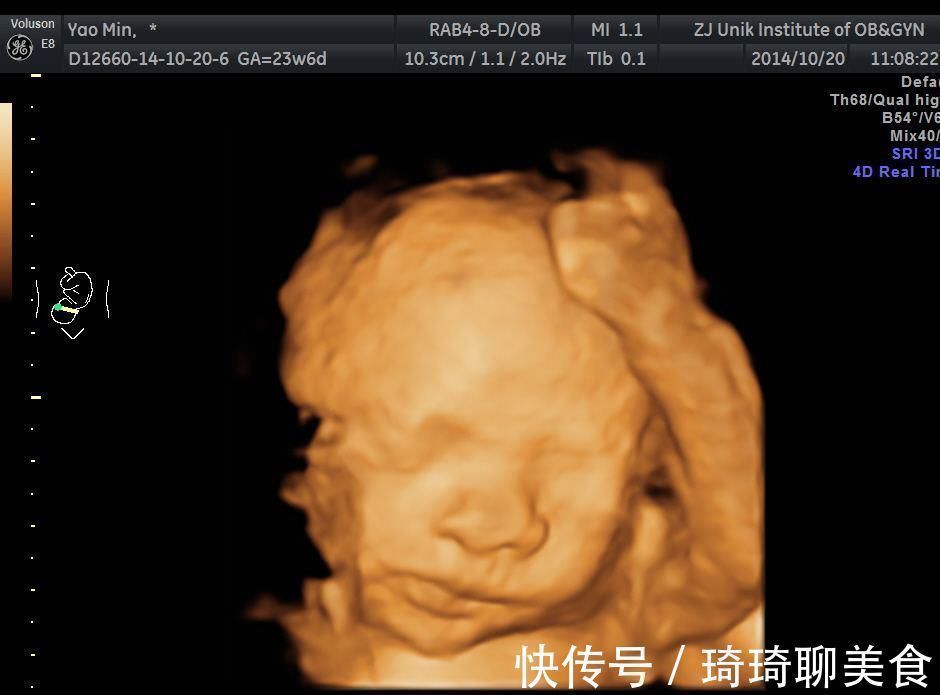

相对来说大一些

做四维彩超时,胎儿还非常小,总体长度约30厘米,头部的长度大约是15厘米,胎儿还非常瘦小,基本上是皮包骨头,面部只有鼻子是突出的,其他都是下凹或者平面状态,所以鼻子显得格外突出,相对来说比较大。等出生后,面部肌肉越来越饱满,眼睛变大了,鼻子的大小也会更加对称了。

成像原理导致的

四维成像的远离不是小孔成像,不是拍的时机照片,而是在二维基础上,加上时间维度,用电脑软件合成的图像。四维彩超会将立体模式进行重建,将胎儿的面部结构更为清晰、更为直观地显示出来,有利于将可靠的依据提供给胎儿面部畸形筛查。